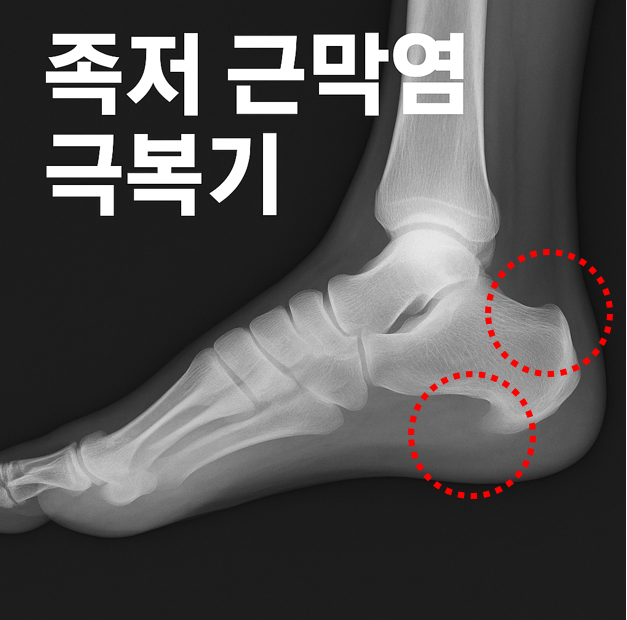

설상가상으로 저는 지금 저의 발은 족저골극(Plantar Spur)과 후종골극(Achilles Spur), 두 가지 모두를 겪고 있습니다.

이제는 달리기는커녕 발바닥 통증으로 걷는 것조차 버거운 하루를 살아가고 있습니다.

족저골극과 후종골극으로 생긴 족저근막염을 치료하기 위하여 병원 재활 트레이닝까지 받았지만, 증세는 낳아지지 않았으며 통증에서 벗어나기까지는 근 일 년이라는 세월을 보내야 했습니다.

족저근막염의 통증은 단순히 발의 문제가 아닙니다.

하루의 시작을 망설이게 하고, 나를 움직이게 하던 삶의 리듬까지 무너뜨립니다.

그래서 통증을 줄이기 위해선 하나의 처방만으로는 부족합니다.